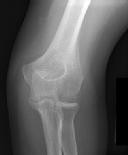

Figures 1 and 2 are the radiographs of a 35-year-old man who has elbow pain after falling from a ladder onto an outstretched hand. Examination reveals elbow pain, swelling, limited motion, and normal neurologic function.